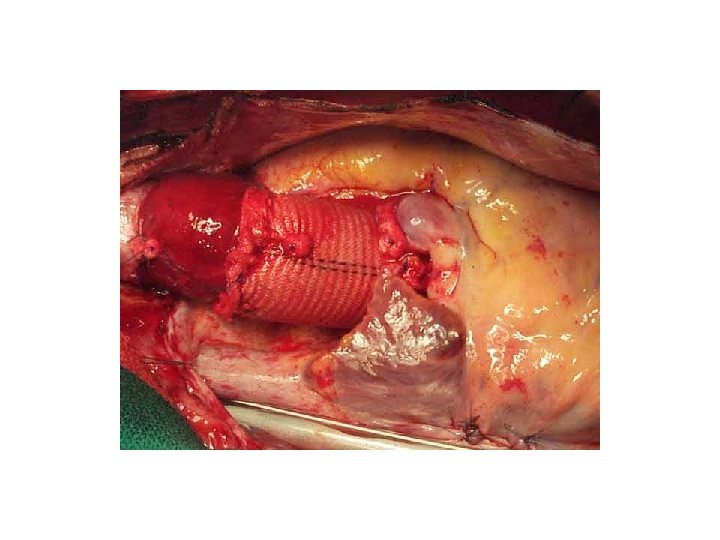

Syftet med akut operation är att förhindra aorta ruptur och tamponad samt att återställa aortaklaffunktionen Dissekerad a asc dissektionsmembran

Falskt lumen Äkta lumen Rakt dacrongraft